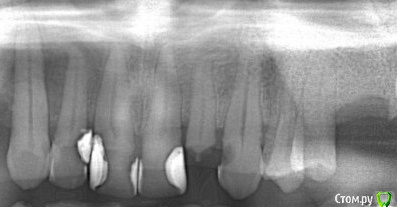

ЛанаМ Опубликовано 8 августа, 2019 Поделиться Опубликовано 8 августа, 2019 Пациентка недавно приходила с жалобами на боль при жевании в 37 зубе. Я отправила ее к другому специалисту, т.к. не уверена, что у меня есть что-то настолько гибкое. А чем лучше проходить такой канал по вашему мнению? Ссылка на комментарий

St. Опубликовано 10 августа, 2019 Поделиться Опубликовано 10 августа, 2019 Пациентка недавно приходила с жалобами на боль при жевании в 37 зубе. Я отправила ее к другому специалисту, т.к. не уверена, что у меня есть что-то настолько гибкое. А чем лучше проходить такой канал по вашему мнению?а еще лучше что нибудь из сплава с памятью формы(хайфлекс. соко или что то подобное) Ссылка на комментарий

ЛанаМ Опубликовано 12 августа, 2019 Поделиться Опубликовано 12 августа, 2019 S1 и S2 это что было? Протейперы? Ссылка на комментарий

St. Опубликовано 12 августа, 2019 Поделиться Опубликовано 12 августа, 2019 S1 и S2 это что было? Протейперы?да Ссылка на комментарий

ЛанаМ Опубликовано 13 августа, 2019 Поделиться Опубликовано 13 августа, 2019 Что-то мне не верится, что они могут так изогнуться. Ломались в каналах с гораздо меньшими изгибами при ковровой дорожке до 20. Ссылка на комментарий

Ico Опубликовано 16 августа, 2019 Поделиться Опубликовано 16 августа, 2019 Что-то мне не верится, что они могут так изогнуться. Ломались в каналах с гораздо меньшими изгибами при ковровой дорожке до 20.Так он ими до WL не рабаотал,только до первого изгиба. Ссылка на комментарий